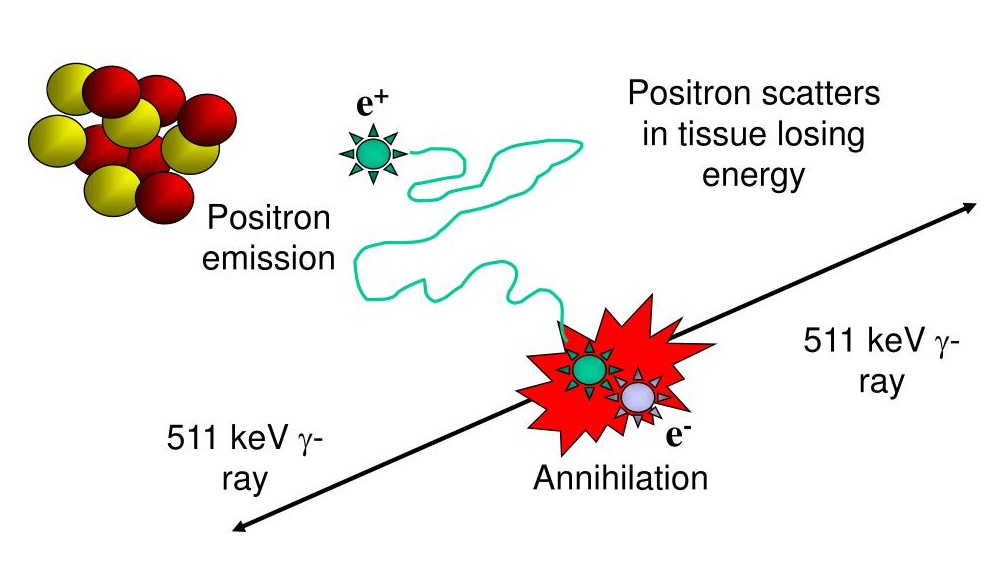

What type of energy interaction does a PET camera pick up on?

Picks up on the energy emitted from an annihilation interaction between an electron and a positron that’s lost energy – positively charged electron

Is a byproduct of beta positive decay

Can you elaborate on how beta positive decay works or takes place? (type of parent, what happens in the nucleus, and what happens to the byproduct)

The parent is unstable and has too many protons → will convert one of the protons into a neutron

As consequence of this conversion, it will create a positron as a byproduct that will get ejected from the nucleus

The positron will travel a length of distance – losing energy until it becomes a positively charged electron

It will then interact with a negatively charged electron and cause an annihilation reaction

How many photons are made during an annihilation reaction?

2 photons are emitted – one is equal to 511 keV

What is the total energy made when an annihilation reaction occurs?

1.02 MeV – 511 keV + 511 keV

What needs to take place before an annihilation reaction happens?

The positron needs to have reached its rest mass – or else the photons made would be more than 511 keV

No, not all positrons are the same as each one made is by a different parent decay – will have a different amount of energy due to the number of protons in the parent nucleus

What happens if the positron has a lot more energy?

It will be able to travel a farther distance

Elaborate on why there is error associated with PET specific to the distance that the positron travels prior to annihilation

When the positron is made as a byproduct of beta positive decay, it’s ejected from the nucleus and will travel a distance away due to it being high in energy

As a PET camera detects annihilation reactions, every line of response it detects will have around 0.1 mm of error from the range of the positron traveling a distance